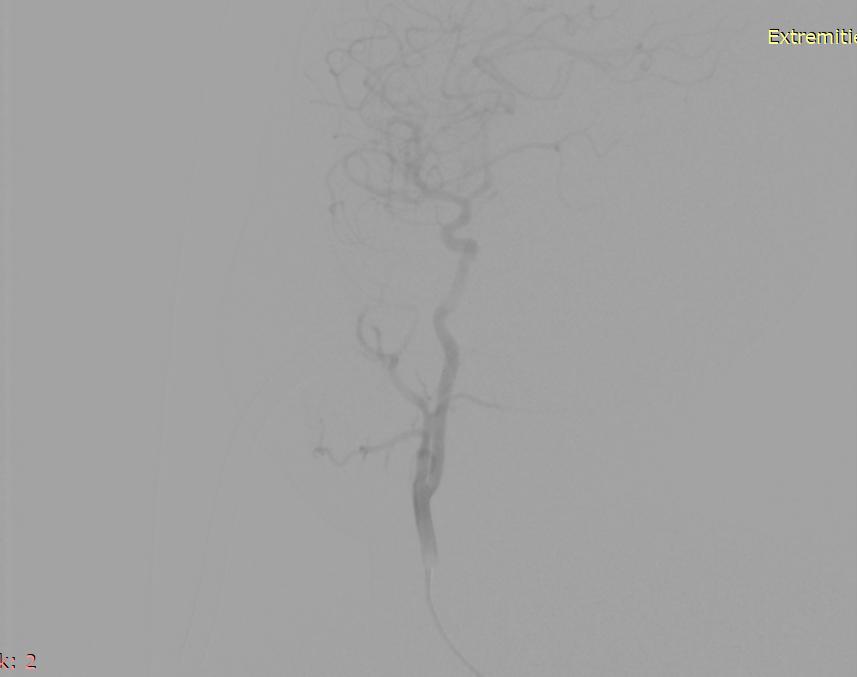

栓塞后